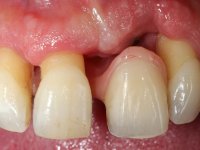

Case 1: clinical

Male patient, 55 years old, smoker. Presented to our dental appointment with a dental implant placed in the area of tooth 21. The gingival architecture in the area lack interdental papilla and showed a vertical deficiency of the soft tissue. Adjacent teeth had significant root exposure.

I’ve decided to rehabilitate the dental implant by closely mimetizing the crown and the root of the adjacent teeth, as well as the gingiva close to the soft tissue deformity. Thus, the prosthetic component would integrate three parts: crown, root and gingiva.

The angulation of the dental implant did not allow for a screwed prosthesis. Thus, an anatomical abutment was used and the crown margin was milled 1mm infragingival, to allow the removal of the cement. The prosthetic component included a ceramic part emulating the crown and the root of the adjacent teeth, and a gingival part to compensate the soft tissue deficiency. Periodontal surgery to regenerate soft tissue in a vertical deficiency is complex and unpredictable, hence this prosthetic option. Although unconventional, this rehabilitation was well accepted by the patient, easy to perform and proved to be aesthetically satisfying and stable over time.